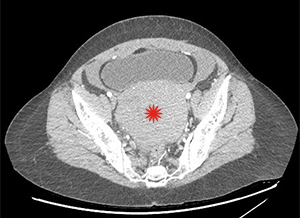

There is a large hemoperitoneum (arrow below) with a massive rectouterine structure (star below) concerning for clot.

We were most concerned about a ruptured ovarian cyst as the patient’s pregnancy test was negative and there was no other obvious cause of blood in the abdomen. She did not have the classic story of onset of pain after intercourse. We did a CT scan because the bedside ultrasound images were difficult to interpret due to the clotted blood. The radiologist suspected ruptured ovarian cyst as the cause of the hemoperitoneum.